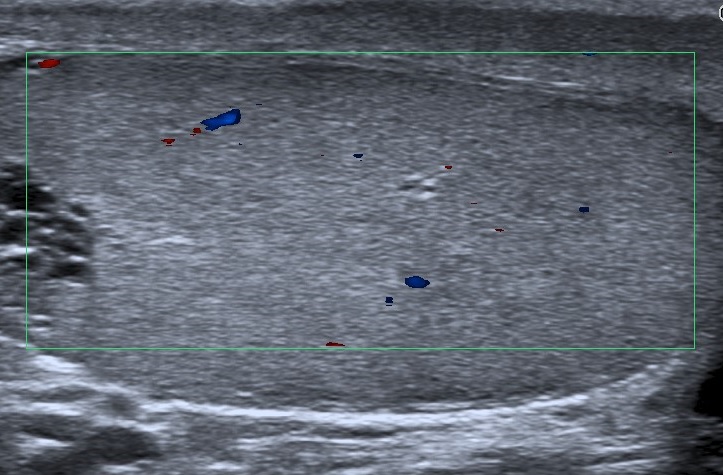

• Se realiza estudio con sonda lineal de alta frecuencia. Se explora el escroto y ambos testículos (figura 1), que presentan tamaño, morfología y ecoestructura normal, así como correcto flujo Doppler (figura 2). A nivel del teste izquierdo, se observa una colección de pequeñas imágenes anecoicas en el mediastino testicular, pseudotubulares. Además, una imagen anecoica, redondeada, quística, a nivel de la cabeza del epidídimo (figura 3).